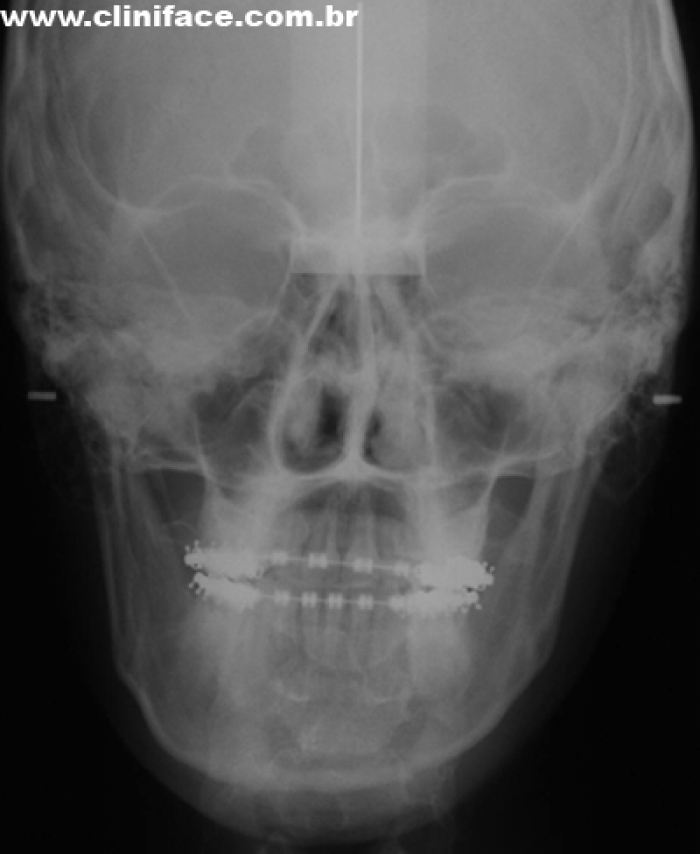

Telerradiografia frontal inicial